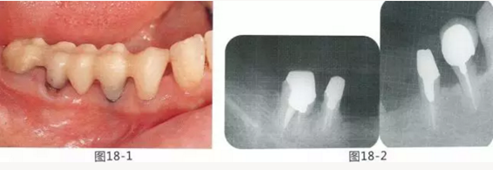

58歲女性,在修復治療前,為了去除牙周袋和獲得附著齦,頰側(cè)進行APF(齦瓣根尖側(cè)轉(zhuǎn)移),FGG(游離齦移植),舌側(cè)進行APF(齦瓣根尖側(cè)轉(zhuǎn)移)進行對應的病例

圖18-1 右上4,5,6,6,7部位,初期治療結(jié)束時牙齦的狀態(tài)。

圖18-2 手術前同部位的口腔X光片。

圖18-4 去除臨時修復體后的頰側(cè)面照。在手術前去除右下5,6,7的金屬樁可以使手術更為方便。右下5,6部位基本看不到角化牙齦。

圖18-5 同部位的舌側(cè)面照片。角化牙齦較少,將牙槽嵴頂預測切開的話很有可能會沒有任何角化牙齦。